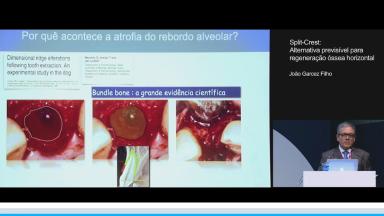

Nesta aula são apresentados os tipos de reabsorção dos rebordos edêntulous e alternativas cirúrgicas conhecidas aplicadas para sua resolução. Atualmente, há inúmeras técnicas encontradas na literatura com boa aplicabilidade clínica para reconstrução do tecido ósseo perdido. A técnica Split Crest é destacada como uma alternativa viável, bem documentada e com aplicação clínica simples, e de fácil execução pelo cirurgião-dentista. Além disso, destacam-se as indicações e os princípios para uso da técnica, e o passo a passo da mesma para que o sucesso clínico seja alcançado.

- identificar os tipos de rebordos edêntulos

- descrever as técnicas cirúrgicas utilizadas para correção dos rebordos edêntulos

- discutir a técnica Split Crest como uma alternativa para a regeneração óssea horizontal